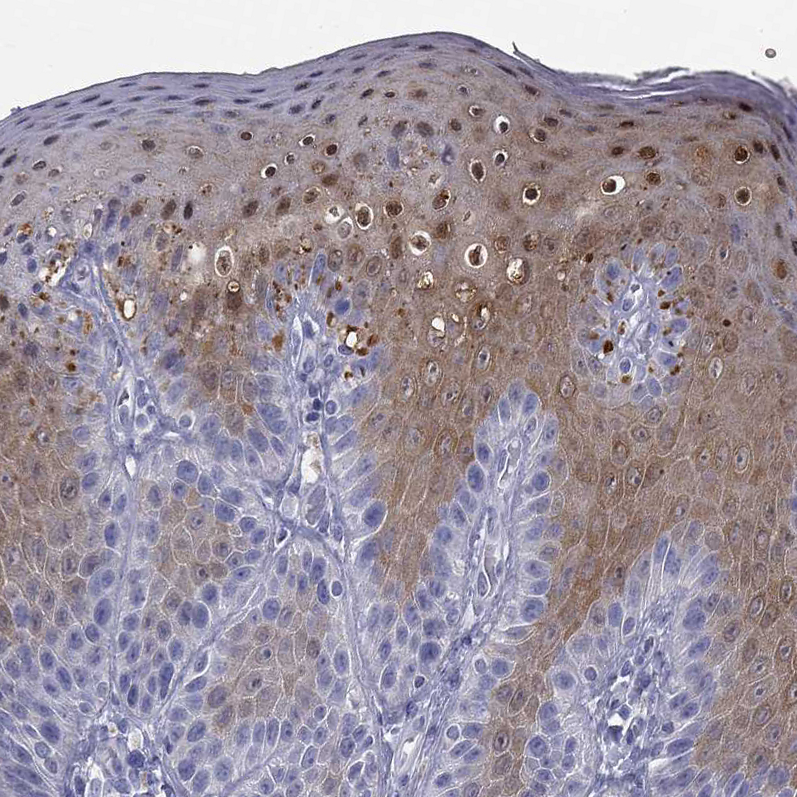

Immunohistochemistry analysis in human skin and lymph node tissues using HPA043539 antibody. Corresponding SULT2B1 RNA-seq data are presented for the same tissues.